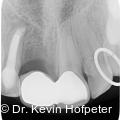

Apikale Läsionen mit ausgeprägter Ausdehnung stellen in der endodontischen Behandlung eine besondere Herausforderung dar. Radiologisch sichtbare Defekte von mehr als einem Zentimeter werden klinisch häufig als Zysten interpretiert. Fotos: © Dr. Kevin Hofpeter